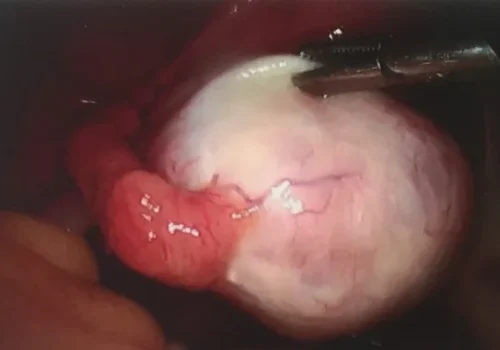

Procedure

She subsequently underwent laparoscopic left ovarian dermoid cystectomy. The pathology revealed a benign dermoid cyst with a molar tooth. This large area of sharp calcification is likely to have caused the pain.